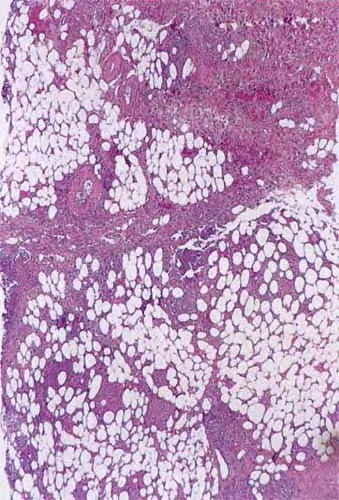

In contrast to erythema nodosum that is mainly a septal panniculitis, erythema induratum (nodular vasculitis) initially is mainly a lobular panniculitis due to vasculitis that produces ischemic necrosis of the fat

lobules with relatively less involvement of the structures of the septa. The fat necrosis can be extensive, caseous as well as coagulative, and elicits granulomatous inflammation . Epithelioid cells and giant cells form broad zones of inflammation surrounding the necrosis but also can form well-delimited granulomas of the tuberculoid type . Ziehl-Neelsen stains do not reveal intact mycobacteria . In approximately one third of cases, granulomas are sparse or absent and lymphocytes and plasma cells predominate . Both the tuberculoid granulomas and lymphoid infiltrate extend between the fat cells, largely replacing them.

Vascular changes are extensive and severe. Arteries and veins of small and medium size show infiltration of their walls by a dense lymphoid or granulomatous inflammatory infiltrate  associated with endothelial swelling and edema of the vessel walls and fibrous thickening of the intima .

Thrombosis and occlusion, or just compromise, of the lumen can produce extensive ischemic and caseous necrosis of the fat in about half of the cases . Extensive necrosis leads to involvement of the overlying dermis and subsequent ulceration. The necrotic fat contains large fat globules, with surrounding amorphous, finely granular, eosinophilic material with some pyknotic nuclei. Later lesions contain many foamy histiocytes surrounding areas of fat necrosis.